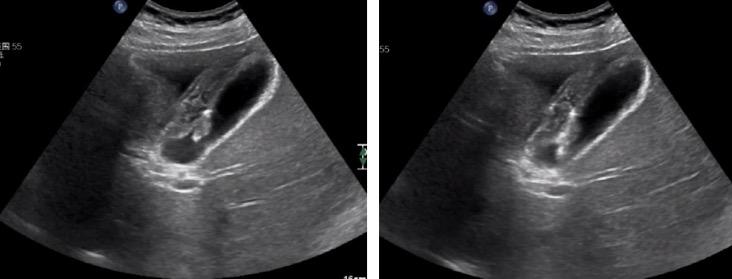

患者男,49岁,2年前体检发现“胆囊息肉”,无疼痛、发热等症状,后定期复查。2019.12彩超复查示:胆囊占位,较前明显增大。欲给予进一步治疗,遂至我院,以“胆囊占位”入住我科。例行超声检查,胆囊内可探及一高回声团,大小约16.2mmx11mm,后伴彗尾,不随体位移动。影像提示:胆囊占位(考虑腺瘤)。

进行胆囊脂餐实验,让患者口服油腻食物,半个小时后再行超声检查,通过前后胆囊的大小变化来判断胆囊的收缩功能。

由此可得,该患者胆囊收缩率约为80%,胆囊收缩功能正常,具有保留胆囊的意义。(一般情况下缩小50%以上,可视为胆囊收缩功能正常)